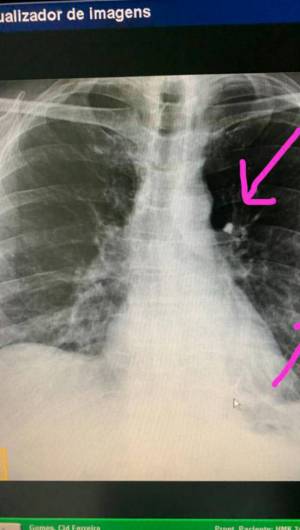

O senador licenciado Cid Gomes (PDT) passou por exame realizado pela Perícia Forense (Pefoce), por ter sido levantado rumor de que o tiro teria sido de bala de borracha. A irmã do senador, Lia Gomes, enviou fotos do exame com detalhe da lesão sofrida por ele.

O senador segue internado no hospital Monte Klinikum, em Fortaleza, após ter sido atendido no Hospital do Coração de Sobral. Segundo o último boletim médico do Monte Klinikum, Cid Gomes teve trauma torácico por arma de fogo, que ocasionou perfuração do hemotórax esquerdo, lesão pulmonar e pneumotórax hipertensivo, segundo o boletim médico do Monte Klinikum.